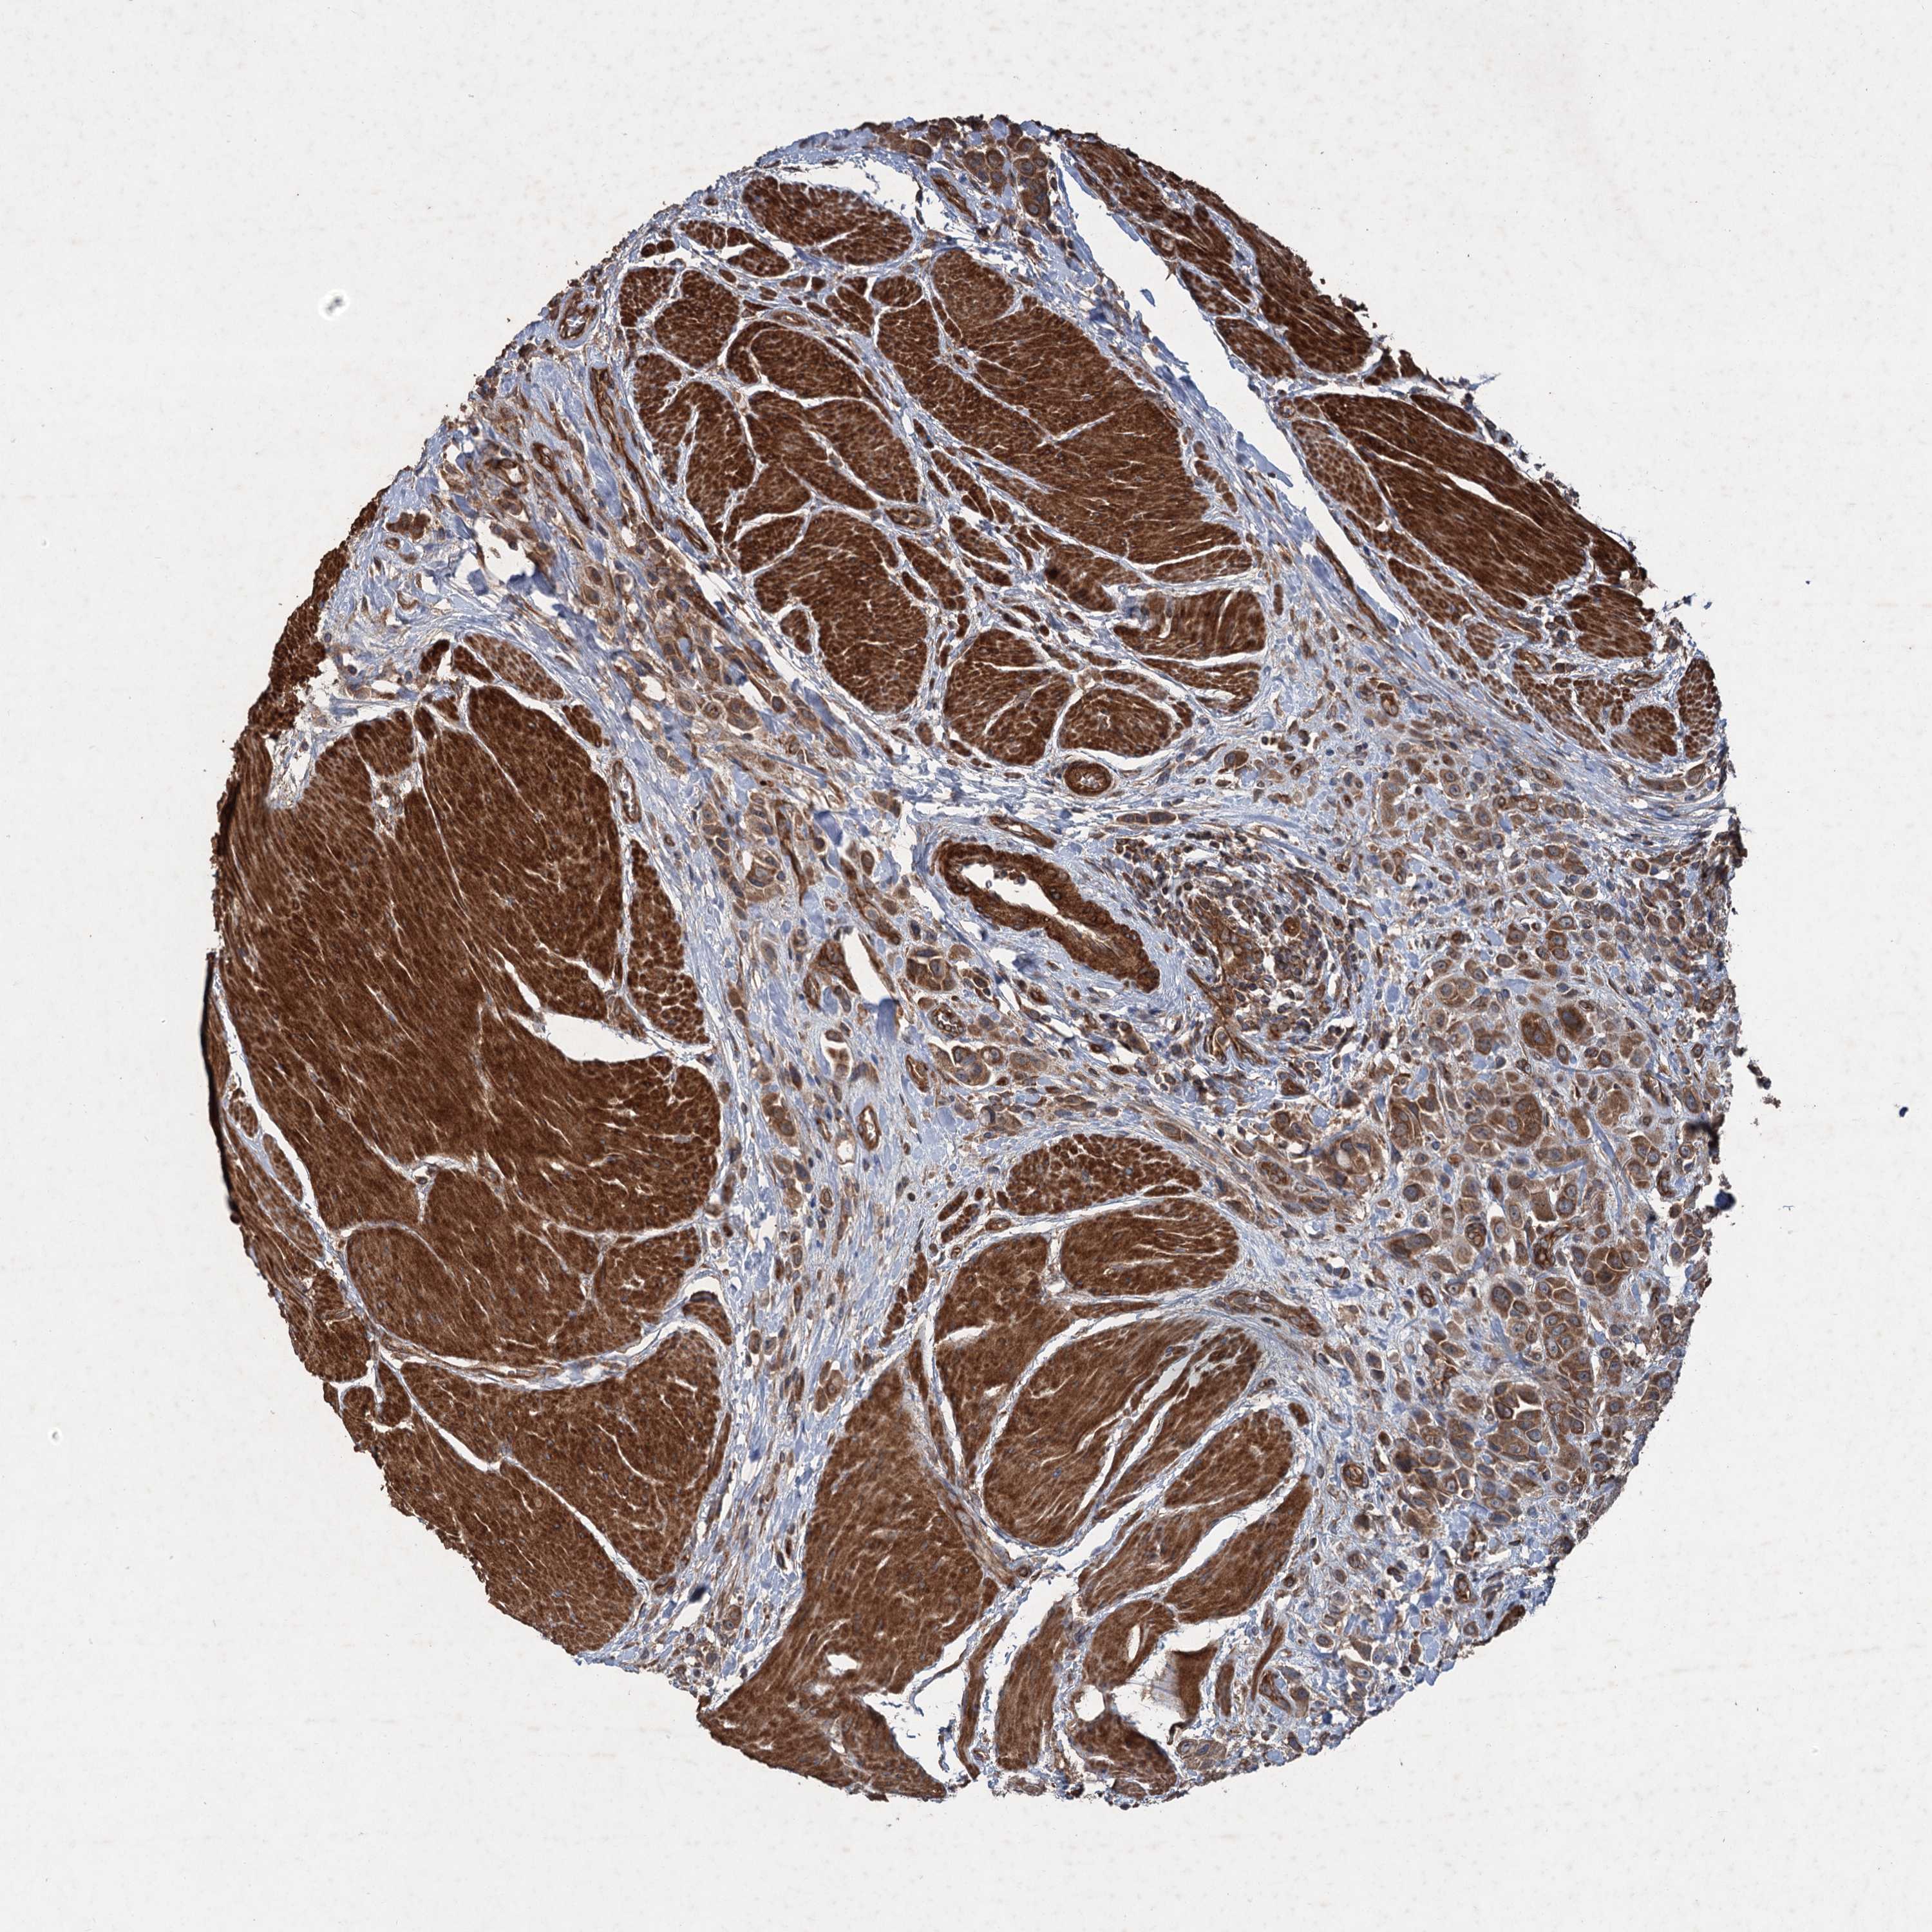

UROTHELIAL CANCER - Protein expressioni

A mouse-over function shows sample information and annotation data. Click on an image to view it in a full screen mode. Samples can be filtered based on level of antibody staining by selecting one or several of the following categories: high, medium, low and not detected. The assay and annotation is described here.

Note that samples used for immunohistochemistry by the Human Protein Atlas do not correspond to samples in the TCGA dataset.

Antibody stainingi

Antibody staining in the annotated cell types in the current human tissue is reported as not detected, low, medium, or high, based on conventional immunohistochemistry profiling in selected tissues. This score is based on the combination of the staining intensity and fraction of stained cells.

Each image is clickable and will lead to virtual microscopy that enables deeper exploration of all samples and also displays staining intensity scores, fraction scores and subcellular localization as well as patient and tissue information for each sample.

Antibody HPA039332

Staining

High

Medium

Low

Not detected

Intensity

Strong

Moderate

Weak

Negative

Quantity

>75%

75%-25%

<25%

None

Location

Urothelial carcinoma, High grade

Urothelial carcinoma, Low grade

Urothelial carcinoma, NOS